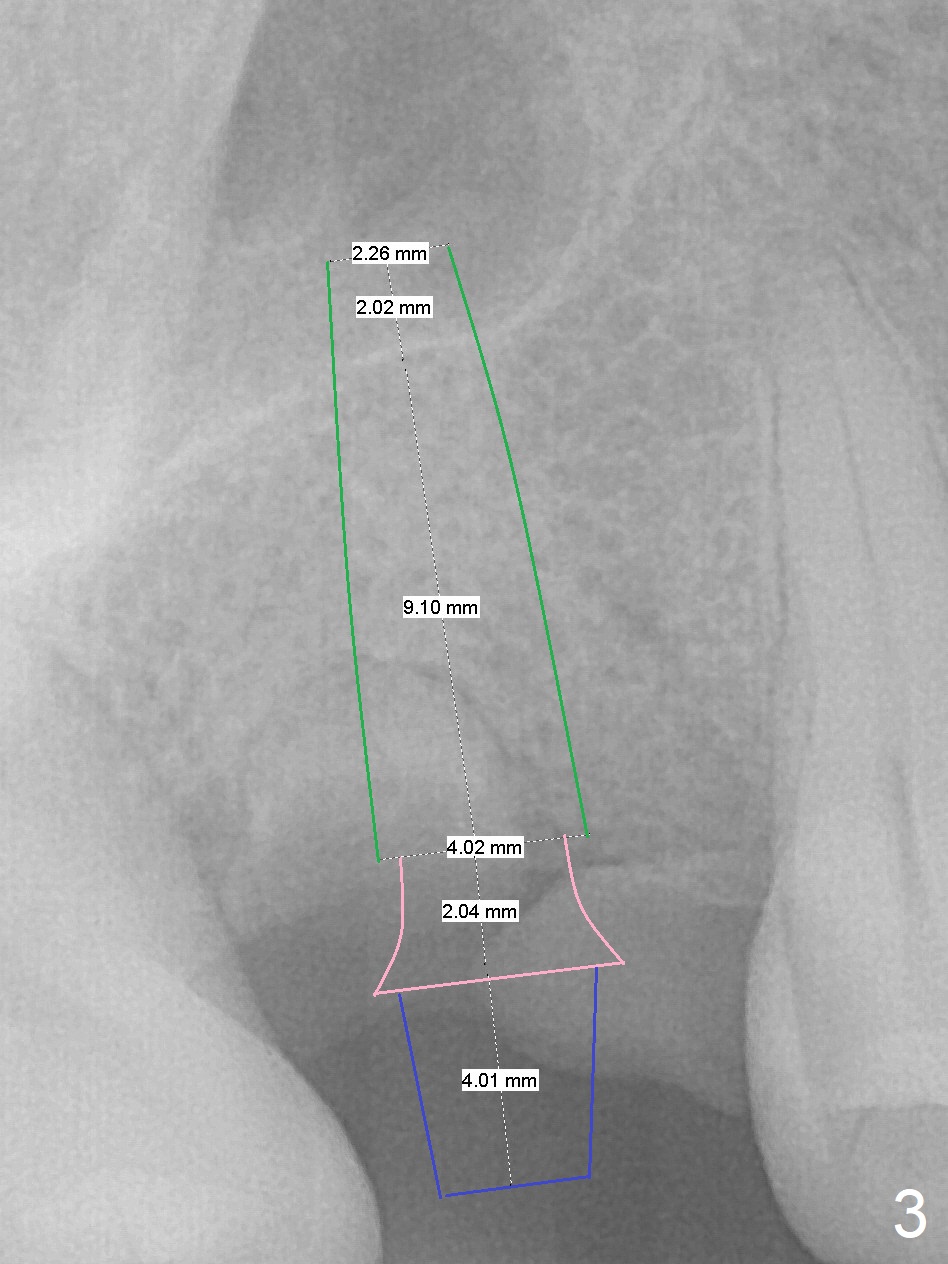

A 45-year-old woman has poor dentition due to dental phobia (Fig.1).  The tooth #3 has residual roots (Fig.2 *).  The initial depth will be 9 mm with starter drill, 2 mm drill (parallel pin, PA) and 3.2 mm Magic Drill (Fig.3).  Use 4x11 mm dummy implant for sinus lift for the last 2 mm.